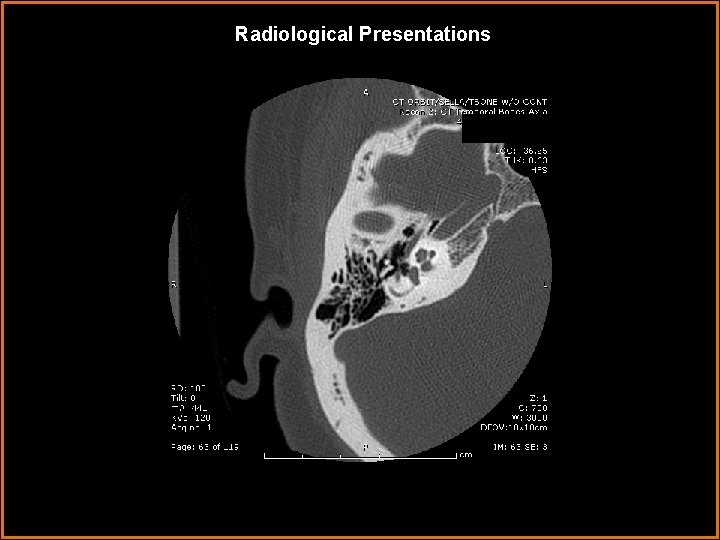

Findings and Differentials Findings: Soft tissue 5 mm nodule arising from the cochlear promontory in the middle ear. Clearly separated from facial nerve (its horizontal segment can be seen on the first several axial slices running anteromedial to posterolat, just under the lateral semicircular canal). Scutum intact, epitympanic recess clear. Differentials: • A. Glomus tympanicum • B. Cholesteatoma • C. Facial nerve schwannoma • D. Persistent stapedial artery

Discussion • Glomus Tympanicum typically presents as pulsatile tinnitis in a middle age female (vascular lesions=pulsatile). It arises from glomus bodies along the tympanic branch of CN IX, called Jacobson’s nerve. On MRI it is an enhancing vascular lesion. It classically arises from the cochlear promontory (arrows below). When large, it tends to engulfs bone but does not erode it. Coronal Axial